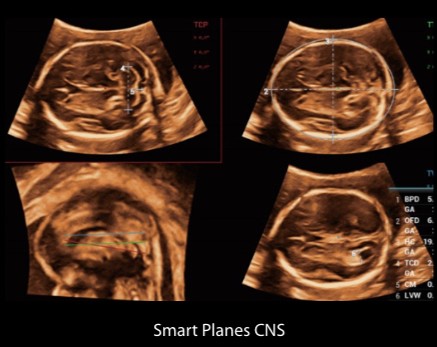

Компютърно решение за изследване на мозъка на плода. Smart Planes предоставя удобен за потребителя инструмент, който значително подобрява ефективността на сканирането чрез повишена точност, съчетана с автоматизирана работа.